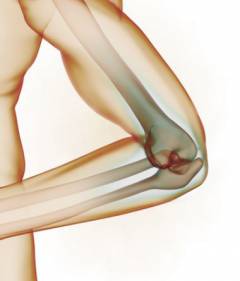

Локтевая область — это место соединения локтевой и лучевой костей с плечевой костью, образующее локтевой сустав. Задняя часть сустава и другие анатомические элементы вне его составляют локоть.

Локтевой сустав

Локтевой сустав — один из самых сложных в организме из-за своей структуры. Он образован тремя костями: плечевой, лучевой и локтевой. Плечевая кость находится между плечом и локтем, а лучевая и локтевая кости составляют предплечье, располагаясь параллельно: лучевая — снаружи, локтевая — внутри.

Локтевой сустав формируется соединением двух костей предплечья и одной плечевой. Его сложность заключается в наличии мелких суставов: плечелучевого, плечелоктевого и лучелоктевого, которые образуются за счет соединения этих костей.